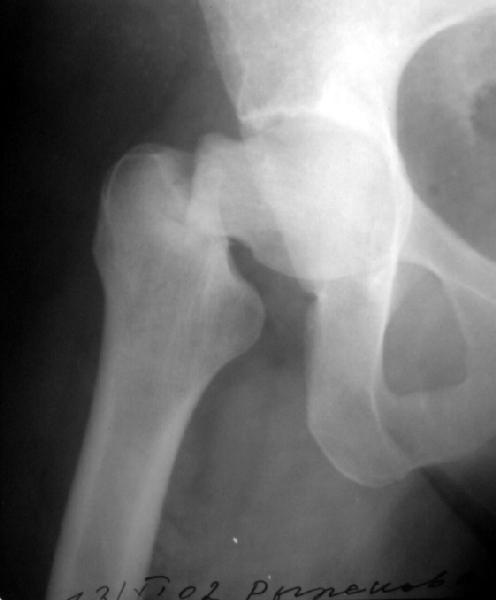

Думаю прежний снимок мало что меняет. Есть базо-цервикальный перелом, на мой взгляд, несвежий. Снимок 11.11.02 технически хуже 13.11.02 и сделан в несколько иной проекции. Жаль что в обеих случаях нет аксиального снимка шейки, на мой взгляд просто необходимого для диагноза.

Сегодня сделали, прилагаю. Качество не очень, но положение отломков видно.

It looks like there is an early fatigue (stress) fracture of the opposite hip as well. I would fix both hips with screws, then get a bone mineral density and other endocrologic work-up

?????Is there a lesion on the opposite neck too!!!!